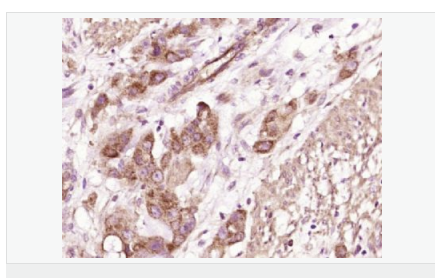

| 產(chǎn)品應用 | WB=1:500-2000 ELISA=1:5000-10000 IHC-P=1:100-500 IHC-F=1:100-500 ICC=1:100-500 IF=1:100-500 (石蠟切片需做抗原修復) not yet tested in other applications. optimal dilutions/concentrations should be determined by the end user. |

| 產(chǎn)品介紹 | Cysteine-rich secretory proteins (CRISPs) represent a family of evolutionarily conserved proteins which may play a role in the innate immune system and are transcriptionally regulated by androgens in several tissues. CRISP proteins are highly expressed in the mammalian reproductive tract and in the venom secretory ducts of some reptiles. CRISP-10 (cysteine-rich secretory protein 10), also known as CocoaCrisp and Trypsin inhibitor Hl, is a 500 amino acid protein containing 2 LCCL domains, which are thought to function as autonomous folding domains used to construct modular proteins through exon shuffling. CRISP-10 differs from other CRISP proteins in that it does not contain the 10 conserved cysteine residues or ICR domains that are usually conserved throughout the CRISP family. Subcellular Location: Secreted. Similarity: Belongs to the CRISP family. Contains 2 LCCL domains. SWISS: Q9H336 Gene ID: 83690 Database links: Entrez Gene: 83690 Human SwissProt: Q9H336 Human Unigene: 436542 Human Important Note: This product as supplied is intended for research use only, not for use in human, therapeutic or diagnostic applications. |